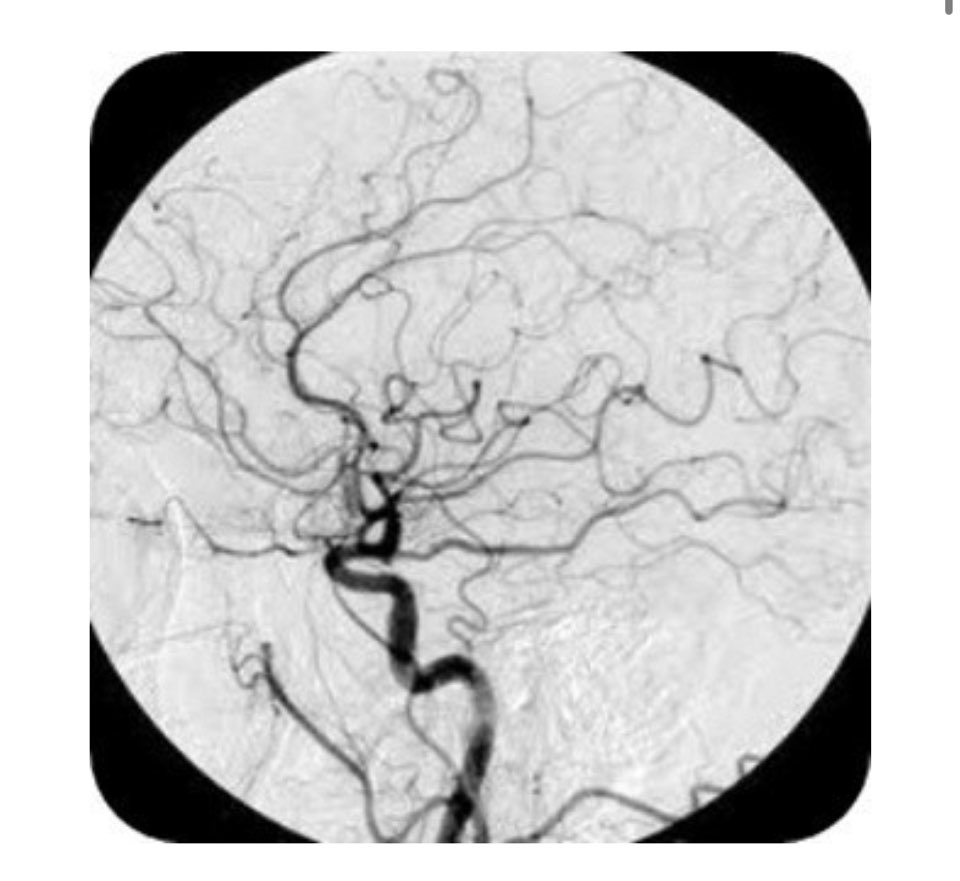

모야모야병은 대뇌에 혈류를 공급하는 데 중요한 역할을 하는 혈관과 모야모야 혈관이라는 작은 이상혈관이 내동맥 끝에서 좁아지는 질환으로 특별한 원인 없이 발생하는 것으로 알려져 있습니다.

일본 스즈키가 뇌혈관 동맥 조영상에서 '담배 연기가 피어오르는 모습'을 뜻하는 '모야모야'라는 이름이 붙었습니다.

모야모야병은 증상 의심이 가장 중요하며 CT, MRI, MRA, 뇌혈관조영술 등 영상진단이 필수입니다.